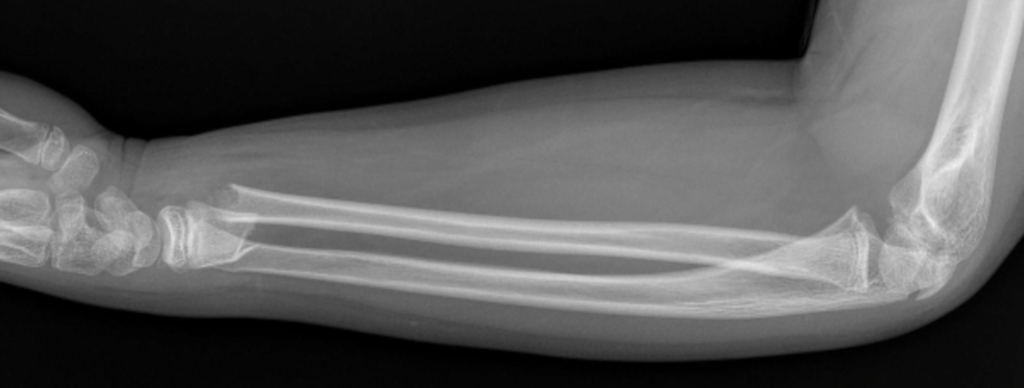

Fratura fechada

Fratura deslocada

Fratura em “galho verde”

Fratura aberta ou exposta

Fratura subperiostal

Fratura frisária